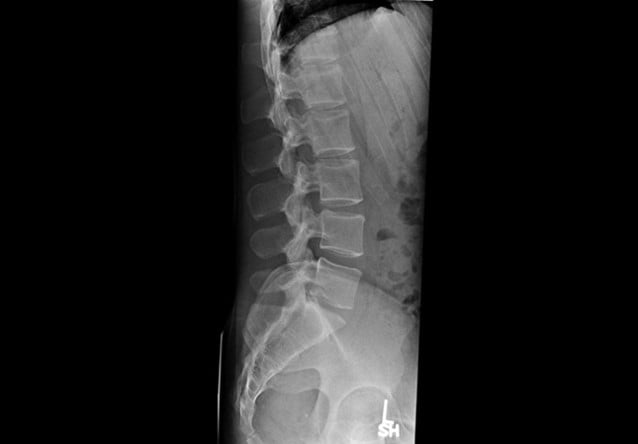

Case courtesy of Dr Hani Makky Al Salam, Radiopaedia.org, rID: 18568

Given the patient’s history of a fall along with spinal tenderness, you order an x-ray that shows an acute T12 compression fracture. Subsequent CT imaging shows an absence of ligamentous injury or cord involvement. Pain control is achieved using IM ketorolac, a lidocaine patch, and calcitonin nasal spray. Spine surgery is consulted and recommends non-operative management. The patient is instructed to follow up with her primary care physician and spine surgeon and endorses understanding.